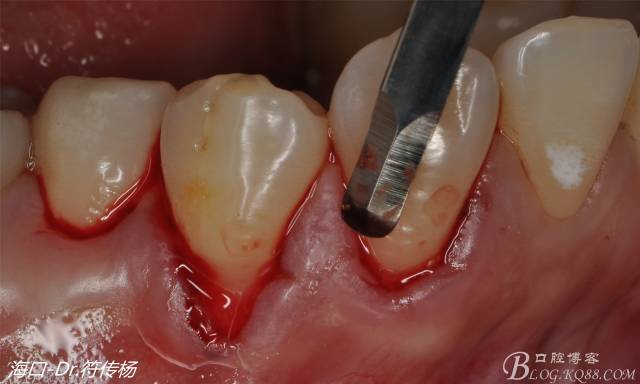

接著從腭部上皮下取出結(jié)締組織

確定取出結(jié)締組織長度是否適當(dāng)

腭部使用水平懸吊縫合更利于壓迫止血

受植區(qū)建議使用雙交叉垂直懸吊縫合術(shù)來固定結(jié)締組織并能讓齦瓣更貼合根面利于術(shù)后一期愈合